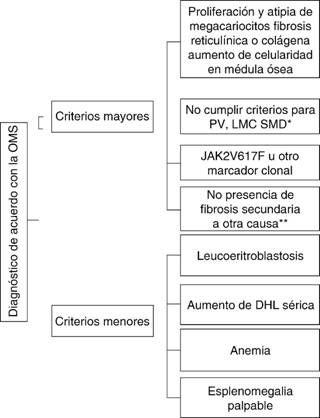

En 2008, la OMS definió los criterios diagnósticos para mielofibrosis primaria basados en una combinación de características clínicas, morfológicas, citogenéticas y moleculares.3 Para establecer el diagnóstico se requieren tres criterios mayores y dos menores (Figura 5).

*PV = policitemia vera, LMC = leucemia, mieloide crónica, SMD = síndrome mielodisplástico, **infección, enfermedades inflamatorias, metástasis, etc.

Figura 5: Diagnóstico para mielofibrosis.